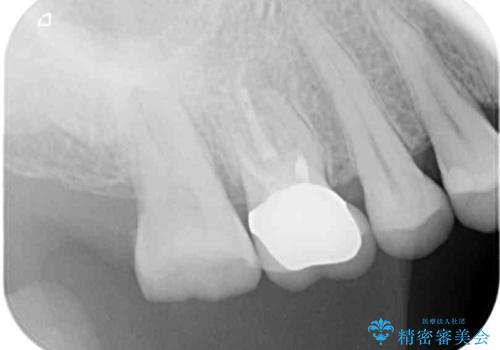

- 眠れないほどの激痛で、噛むと涙が出るほど痛むとのことで来院された患者様です。

咬合力が極めて強く、診査の結果、強大な咬合力により歯内の神経組織が炎症を起こしていることが予想されました。

神経組織は失活しておらず、冷たいもの対する痛みはそれほど強いものではなかったので、場合によっては歯が破折しており、抜歯が必要となる可能性が示唆されました。

患者様と相談し、まずは神経組織を取り除く前提で処置を開始し、その過程で歯の破折が認められた場合には抜歯することとしました。